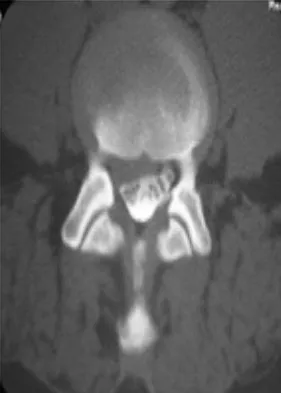

A 35-year-old patient has right hip pain. Figures 34a and 34b show the coronal MRI scan and the biopsy specimen. What is the most likely diagnosis?

Explanation

Question 91